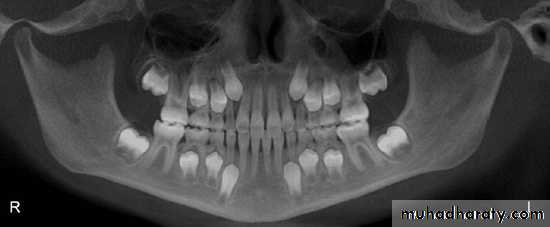

Sever Dental Flourosis. (Case 1)

12

Severe Dental Flourosis. (Case 2)

13